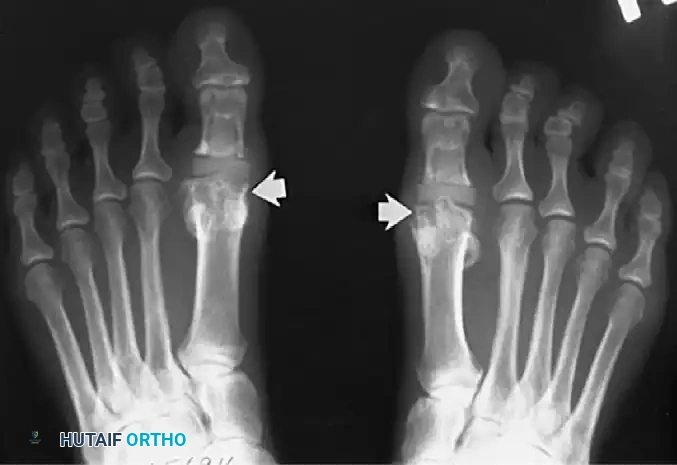

Image

Anteroposterior and oblique views demonstrating severe hallux rigidus with extensive periarticular osteophyte formation and joint space obliteration.

In many instances, hallux rigidus presents bilaterally, necessitating a comprehensive evaluation of the contralateral foot to plan for staged or concurrent interventions.